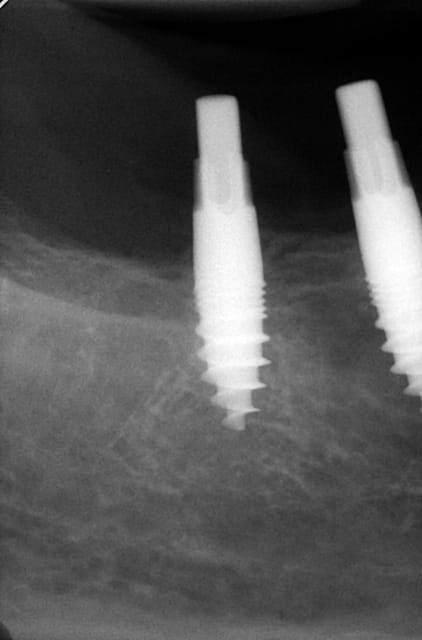

pour répondre à ta question : depuis 1994 , oui d ailleurs dans un des cas présentés tu as une radio après 10 ans :-)! (46 47 )

Maintenant concernant la demande de scans : je poste ce cas, une patiente vient me voir avec son scan car elle a consulté d'autres "spécialistes" et on lui refuse la pose d'implant secteur 4 où alors avec greffe préalable..Ca se discute..pas de temps à perdre je sais faire autrement..

Avec la chir trans gingivale technique MIMI ( Oui..un post sur la technique bientôt ..) j'ai pu placer deux 3,5/8mm..aurai je eu le meme résultat avec un lambeau..j'en doute..Les couronnes sont en titane. Recul clinique 2 ans ras. Simple efficace rapide moins onéreux satisfaisant pour le praticien et la patiente..